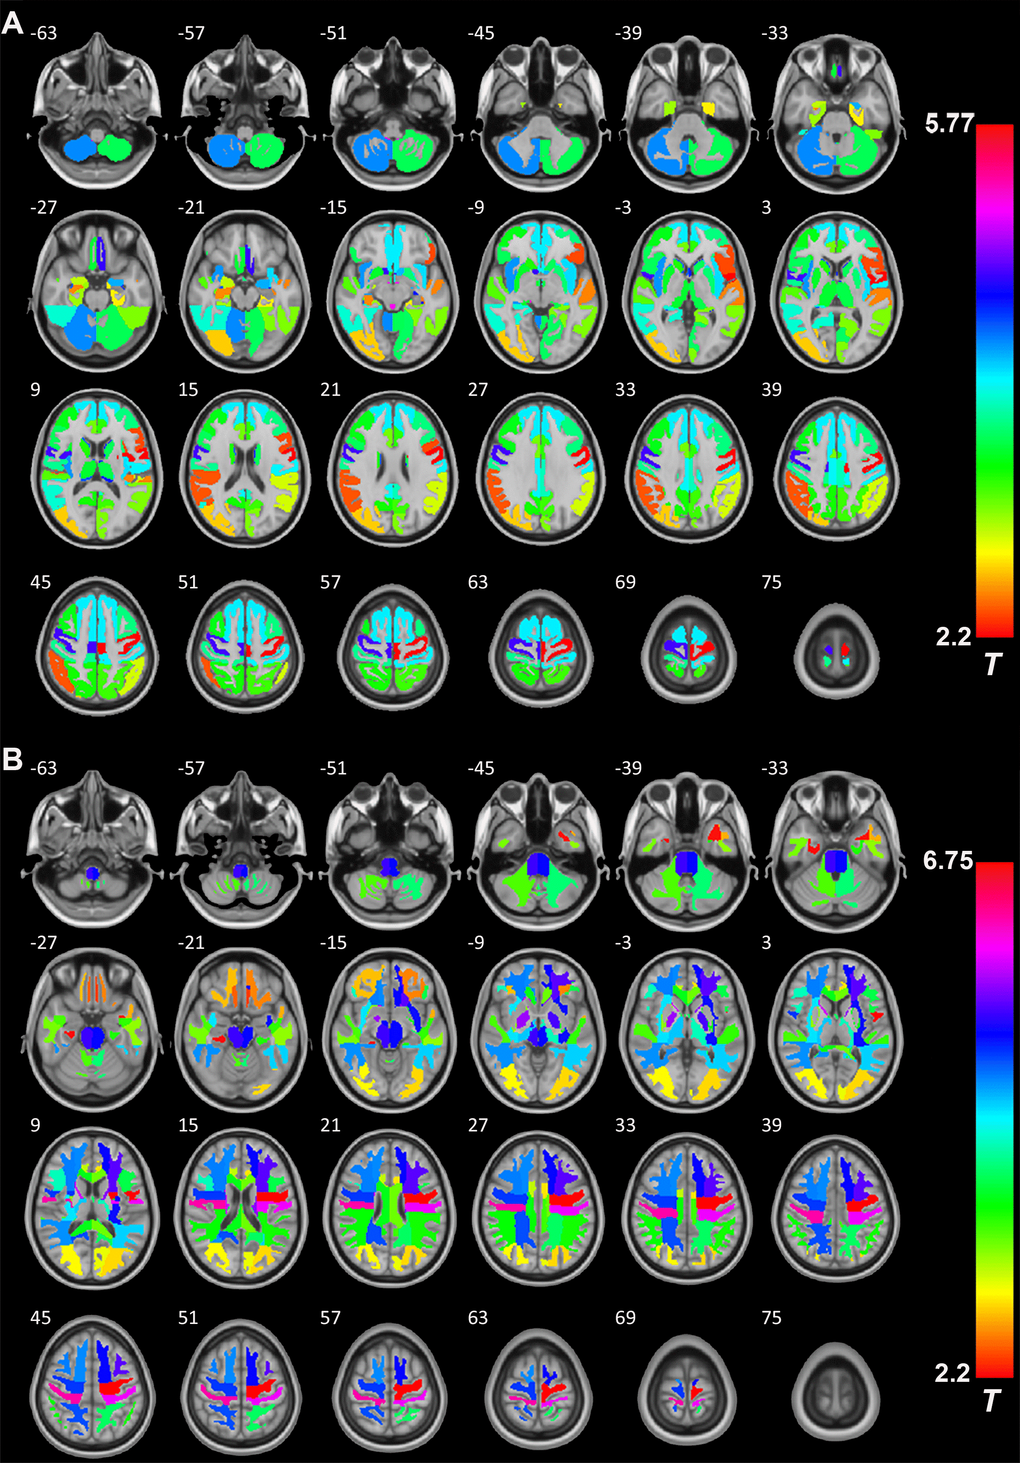

Next, we studied the detailed effects of excess serum GH/IGF-1 levels on the GMV and WMV in different brain regions by comparing the patients with GH-PA and HCs. RBM analysis was used to obtain the average volume of each brain region, according to Hammers’ atlas maps (a total of 68 brain regions). As shown in Figure 5A, the GMV of 54 brain regions (Supplementary Table 1) was significantly greater in the patients than in the HCs. As shown in Figure 5B, as assessment of the WM revealed that the WMV of 54 brain regions (Supplementary Table 1) was significantly greater in the patients than in the HCs.

Figure 5. The role of GH/IGF-1 in the GMV and WMV of brain regions. (A) RBM analysis showing the increased GMV of 54 brain regions (Supplementary Table 1, from a total of 68 brain regions, Hammers' atlas) in patients with excess GH/IGF-1 production compared to that in HCs. (B) RBM analysis showing the white matter volume (WMV) of 54 brain regions (Supplementary Table 1, from a total of 68 brain regions, Hammers' atlas) increase in patients with excess GH/IGF-1 production compared to HCs. Significance was determined by uncorrected p < 0.05, using two-sample t-tests.